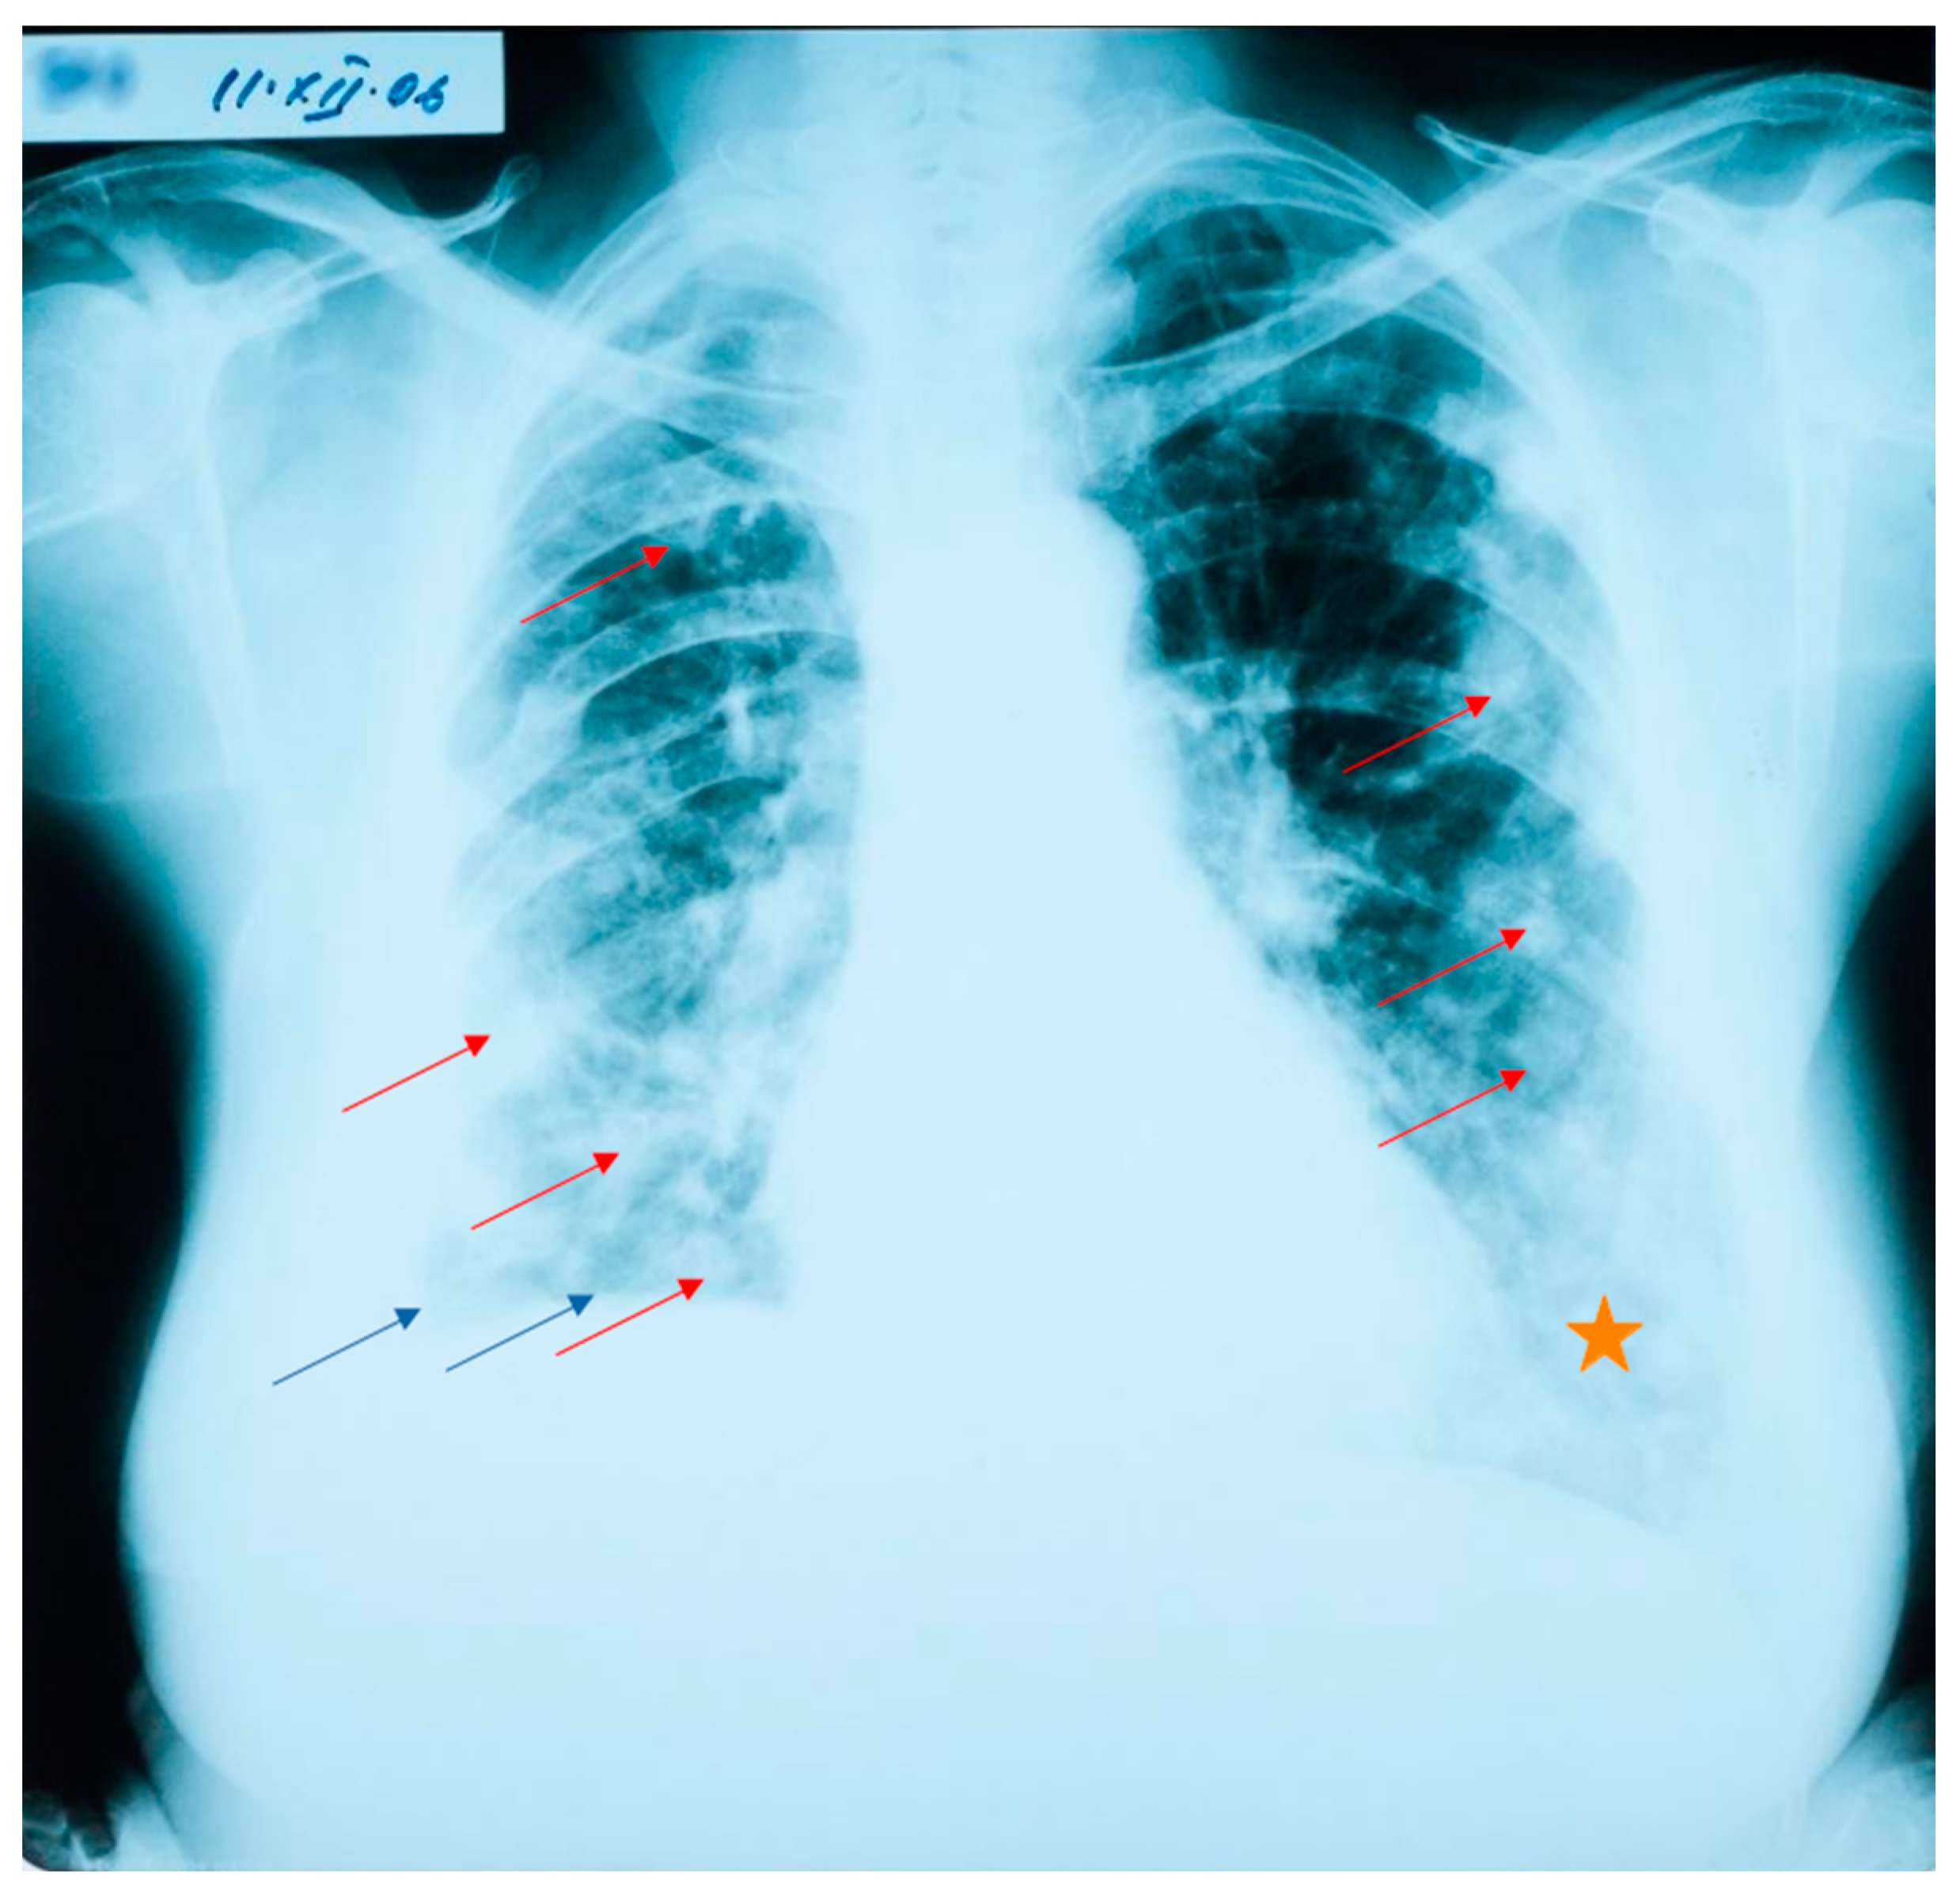

At her check-up in October 2006, the thoracic radiograph raised the suspicion of lung metastases from a cancer of unknown location (numerous 1–2 cm opacities, with bilateral lung dissemination) (Figure 1).

Figure 1. Lung radiograph with numerous bilaterally disseminated opacities. Blue arrows show the elevation of the right diaphragm, and the blunting of the lateral costo-diaphragmatic angle. Red arrows point to round opacities disseminated bilaterally (not all are marked, as to not overcrowd the image). The orange star denotes an area with a diffuse para-cardiac opacity.